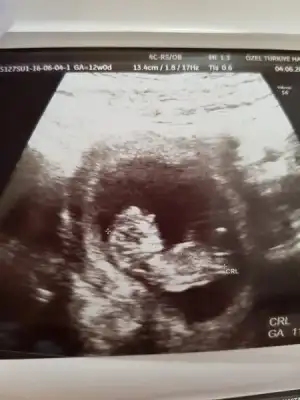

Bana da bakın güzel teyzeler nub dan anlayan tatlı annelerim bir yorumda ben alayım

Var canım bana erkeğe benziyor dedi ama emin değilim dedi bakalım bende çok merak ediyorum emin şekilde ne zaman belli olcak:)

Bana da erkeğe benziyor dedi ama sonra kız diyeceklermis gibi geliyor. Kızım öğrendiğinden beri kardeşim kız olacak diyor. 16. Haftadan sonra neylesir.kızım i 17 haftalikken öğrenmistik kesin olarak

Bazen ben de öyle düşünüyorum aslında daha erken.. Bana da erkek dedi hatta emin konuştu ama belli olmaz.. Genelde 16. haftada belli olur diyorlar..bekleyicez artık ilm çocuk zaten fark etmez ama insan emin olmak istiyor..

benim drumda nerdeyse 15 dk muayene etti cinsiyet için tahminde bile bulunmadı 14.-16. Haftalarda belli olur öncesinde söylenenler tahmindir ve yanılma payı vardır deyip tahminde bile bulunmadı.. Tahminde bulunan doktorlar genital çıkıntıya göre kız yada erkeğe benziyo diyomuş erkepin kemik yapısı farklı lafının doğruluk payı yokmuş... Sonuçta ilk çocuğu olanlar için ne kızımız var ne oğlumuz rabbim sağlıklı ve hayırlı evlatlar nasip etsin inşallah